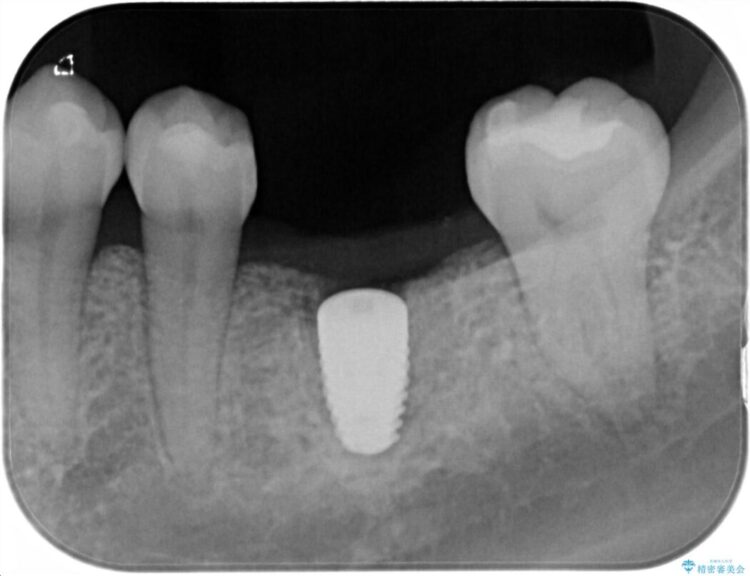

治療計画を立てる上で詳しく精密検査をしたところ、左下の6番目の歯につきまして治療が必要な状態であることが分かり、かぶせ物を外し、内部を確認しました。

結果としては深い部分で根が破折してしまっていました。

破折の処置としては基本的に抜歯が選ばれます。